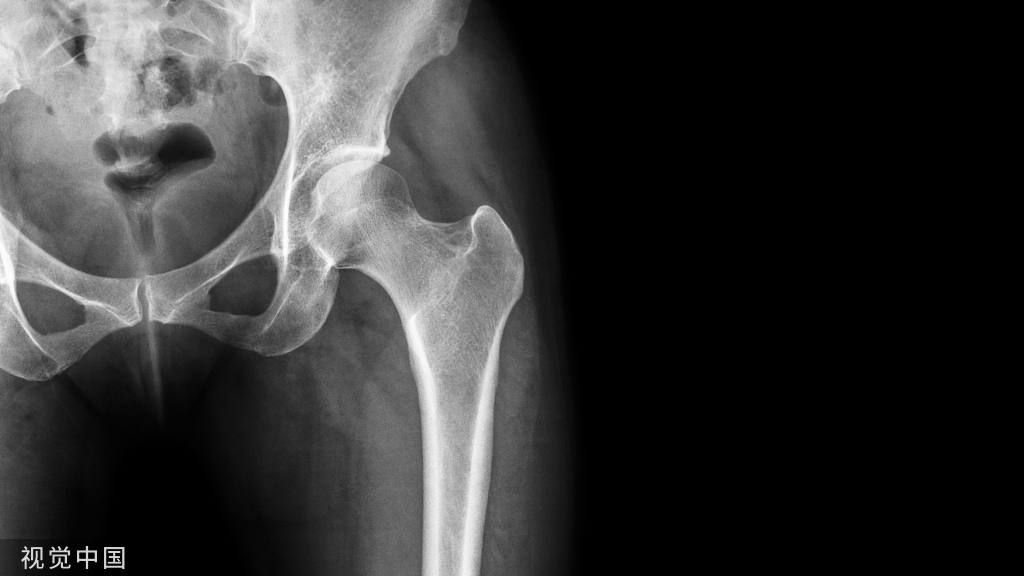

骨科日间手术中心的崛起:大约 70% 的骨科手术最终将在成本较低的ASC环境中进行

根据美国日间手术中心协会(ASC Association)2022年3月的数据,骨科是ASC(Ambulatory Surgery Centers,日间手术中心)中最常见的外科专科。美国Tallahassee骨科诊所首席执行官Michael Boblitz预测,大约 70% 的骨科手术最终将在成本较低的 ASC 环境中进行。